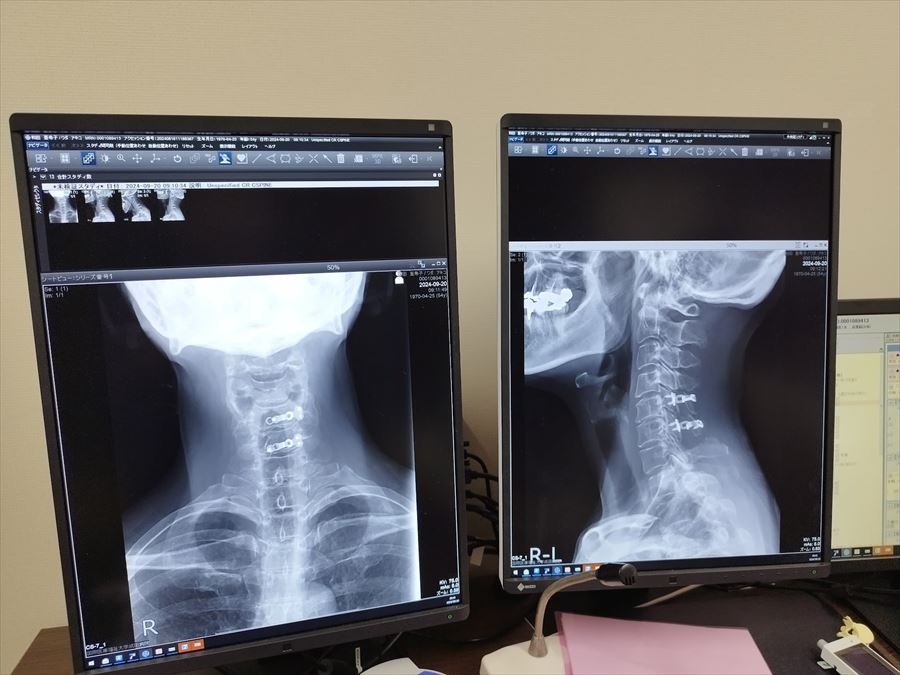

上の左側の写真で、長方形の骨が並んでいるのがわかると思います。その上から3つめと4つめの右側の黒い部分が膨らんで、白い部分が消えています。そこが骨化した靭帯が脊髄神経を圧迫している箇所です。「被膜が破れた電線みたいだな」と思いました。

一か月後検診でCT検査を行い、手術後の首の骨の写真などを見せてもらいました。

脊髄神経が入っているパイプ状のようなところは無事広がり、骨化した靭帯はそのまま残っていますが、スペースが広がったことで、脊髄神経との接触はなくなりました。ボルトもしっかり入って固定されており、何も問題ないとのこと。